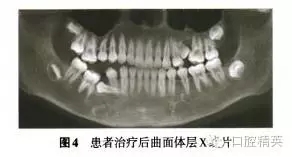

診斷:安氏Ⅲ類亞類錯牙合畸形,5V、5V阻生。治療方案:①拔除V,V,清理V囊腔;②牽引5至正常牙列;③試牽引5,不排除牽引失敗的可能;④使用種植體支抗防止鄰牙壓低和對牙合牙伸長;⑤糾正右側(cè)后牙開牙合,若654粘連導(dǎo)致正畸治療無效,則需調(diào)整治療方案。拔除埋伏乳磨牙時,錐形束CT確認(rèn)下頜神經(jīng)管位于阻生V根分叉下方(圖3),5牙根位于43舌側(cè)。手術(shù)順利拔除埋伏阻生的V、V,8個月后曲面體層x線片示牙槽骨愈合良好,可見4顆第三磨牙牙胚(圖4)。但患者家長放棄牽引治療。